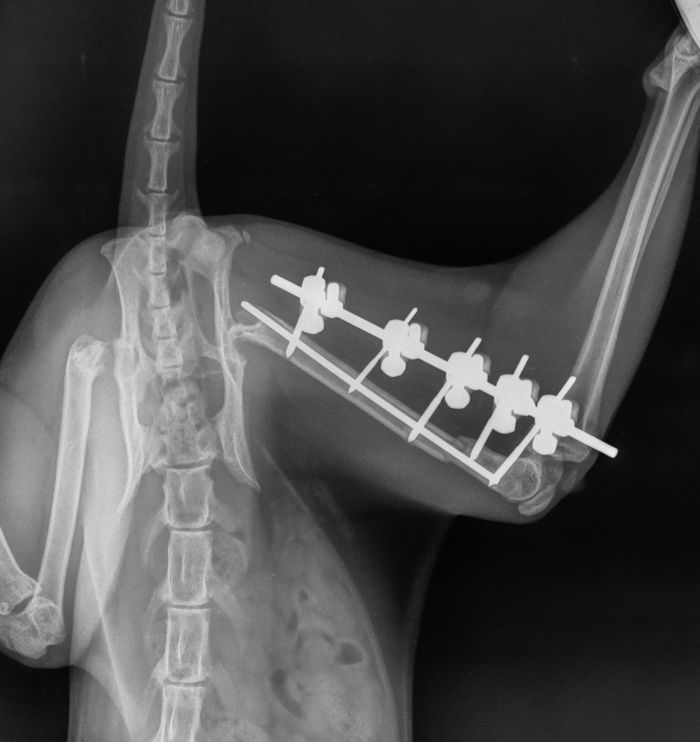

Fixateur externe

Hierbei werden Pinstangen durch die Haut hindurch in die jeweiligen Knochenfragmente gebohrt / in diesen Fragmenten verankert. An den Pinstangen wird dann aussen quer zu den gesetzten PinStangen entweder eine Längsstange oder Kunststoffüberbrückungen angebracht. Die Verwendung eines Fixateur hat seine Vor- und Nachteile die im jeweiligen Einzelfall durch unseren Operateur mit Ihnen besprochen werden.

Fall 1